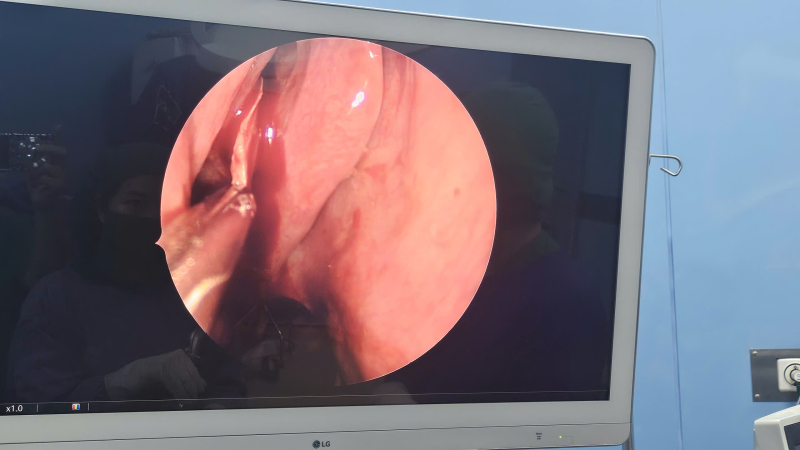

Khối u hốc mũi kích thước lớn được loại bỏ thành công sau phẫu thuật nội soi mũi xoang

Kiểm tra trên màn hình nội soi khoang mũi đã lấy triệt để u